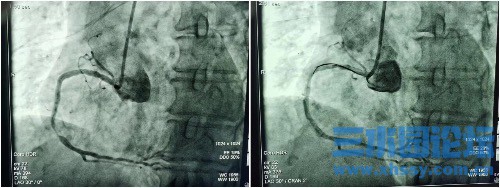

6:55患者送入导管室,7:02穿刺开始,7:11冠脉造影,7:17完成造影并沟通家属,随后于右冠状动脉及左前降支植入支架2枚,血流恢复。8:15手术顺利完成,金奶奶转入CCU,转危为安。

IMG_6490.jpeg

IMG_6491.jpeg

IMG_6492.jpeg